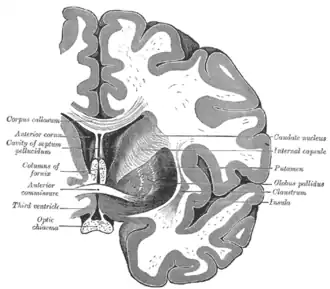

La commissure antérieure, appelée également la commissure blanche antérieure ou encore la précommissure (en latin : commissura anterior), est une commissure inter-hémisphérique qui croise transversalement la paroi antérieure du troisième ventricule[1]. C'est un faisceau nerveux de substance blanche (un paquet d'axones) qui relie les deux lobes temporaux des hémisphères cérébraux à travers la ligne médiane, et il se trouve en avant des colonnes du fornix (les piliers antérieurs trigone du cerveau). Chez la plupart des mammifères existants, la grande majorité des fibres reliant les deux hémisphères traversent le corps calleux, qui est plus de 10 fois plus grand que la commissure antérieure, et d'autres voies de communication passent par la commissure de l'hippocampe ou indirectement, via des connexions sous-corticales. Néanmoins, la commissure antérieure est une voie importante qui peut être distinguée clairement dans les cerveaux de tous les mammifères.

Dans une section sagittale, la commissure antérieure est de forme ovale, ayant un long axe vertical qui mesure environ 5mm.

Les fibres de la commissure antérieure peuvent être tracées latéralement et postérieurement de chaque côté au-dessous du corps strié vers la substance du lobe temporal.

Elle sert à relier les deux lobes temporaux, mais il contient également des fibres décussantes des tractus olfactifs, et fait partie du tractus néospinothalamique pour la douleur. La commissure antérieure sert ainsi à relier les deux amygdales.